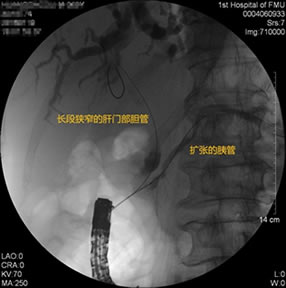

胃毕-Ⅱ术后肝门部胆管狭窄 胃毕-Ⅱ术后金属支架植入

胃毕-Ⅱ术后球囊扩张狭窄胆管 胃毕-Ⅱ术后支架植入 胃毕-Ⅱ术后胆管胰管扩张